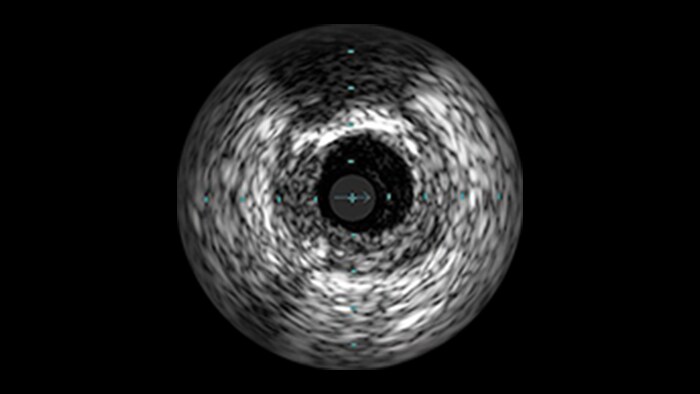

IVUS

Intravascular ultrasound (IVUS) provides images from within the vessel to accurately assess and optimize your treatment plan.

IVUS co-registration

Software helps you understand precisely where the disease begins and ends and guides your pre-and post-strategy decisions for improved outcomes.